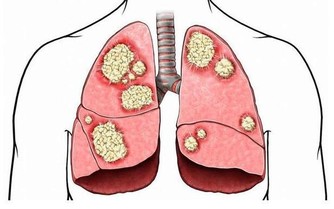

(圖片來源) 將成品存在有蓋的玻璃瓶中,放入雪櫃。 每天早飯前空肚服用一湯匙。 吃上一個月以後去醫院做次檢查, 會發現血管幹乾淨凈,堵塞的地方已經全通了! (文章來源) 心血管疾病很常見, 想打通血管,可以試試這個配方! 不過改變生活習慣更重要喔...!